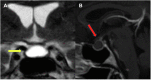

Spontaneous Near-Resolution of a Rathke's Cleft Cyst

Fig. 2